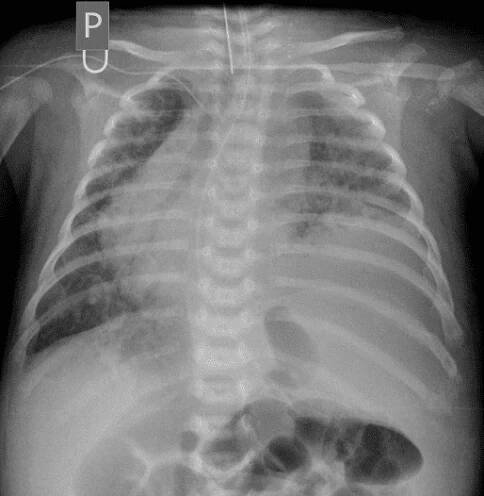

Česká Neonatologická Společnost •

Fluidothorax (fluidotorax) znamená přítomnost tekutiny v pleurálním prostoru, tj. v prostoru okolo plíce. Může být jednostranný nebo oboustranný a může mít celou řadu příčin. Je-li fluidothorax tvořen krví, hovoříme o hemothoraxu, a je-li…

Fluidothorax, pleurální výpotek, pohrudniční výpotek (laicky "voda na plicích") je lékařský termín, označující patologické nahromadění tekutiny v prostoru kolem plíce v tzv. pleurální dutině mezi pohrudnicí (parietální pleura) a poplicnicí (viscerální pleura). Fluidothorax je obecný název, který se dále konkretizuje dle zjištěného složení tekutiny. Obdobný stav je… Wikipedie